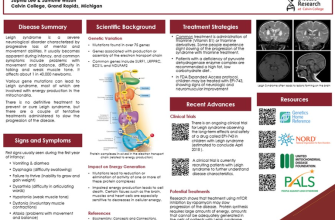

Leigh’s Disease, also known as Leigh syndrome